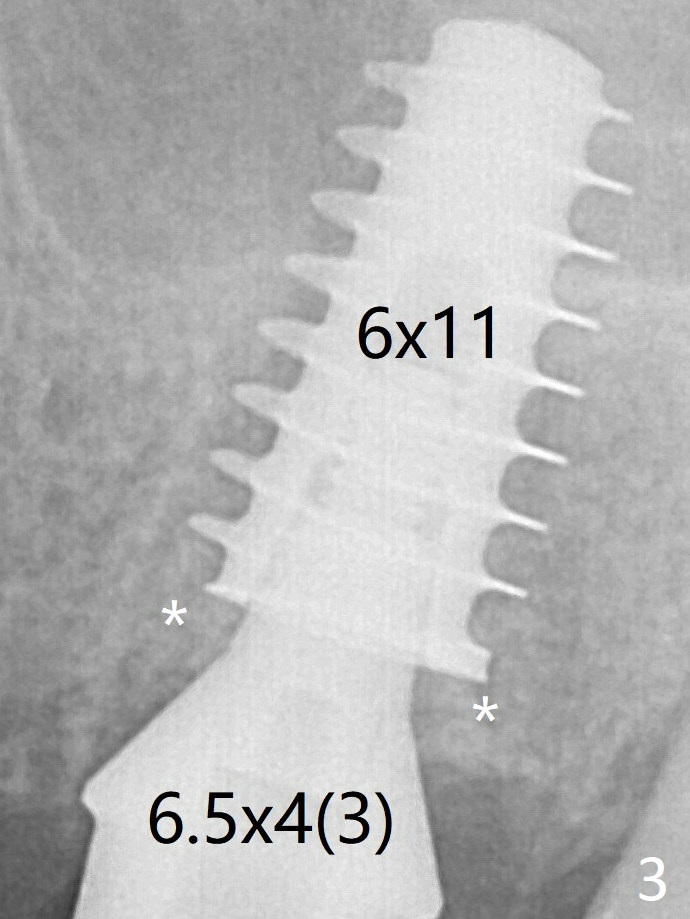

With insertion of Vanilla graft for sinus lift through the buccoapical portion of the osteotomy mentioned above, a 6x11 mm implant is placed with the same trajectory (Fig.2, <40 Ncm). With adjustment of a 6.5x4(3) mm abutment and placement of Vanilla graft in the remaining sockets (Fig.2 *), an immediate provisional is fabricated. The abutment becomes loose again 4 months later. Prior to retightening, a 6 mm profile drill is used. BW shows no bony interference (Fig.5 (opposing tooth occlusal wear; bruxism)), while PA shows the buccal bone, suggesting poor trajectory (guide essential). The gap between the abutment and implant (Fig.6 <) is smaller than that in Fig.3. Thin Septum Last Next Xin Wei, DDS, PhD, MS 1st edition 01/17/2020, last revision 12/19/2020